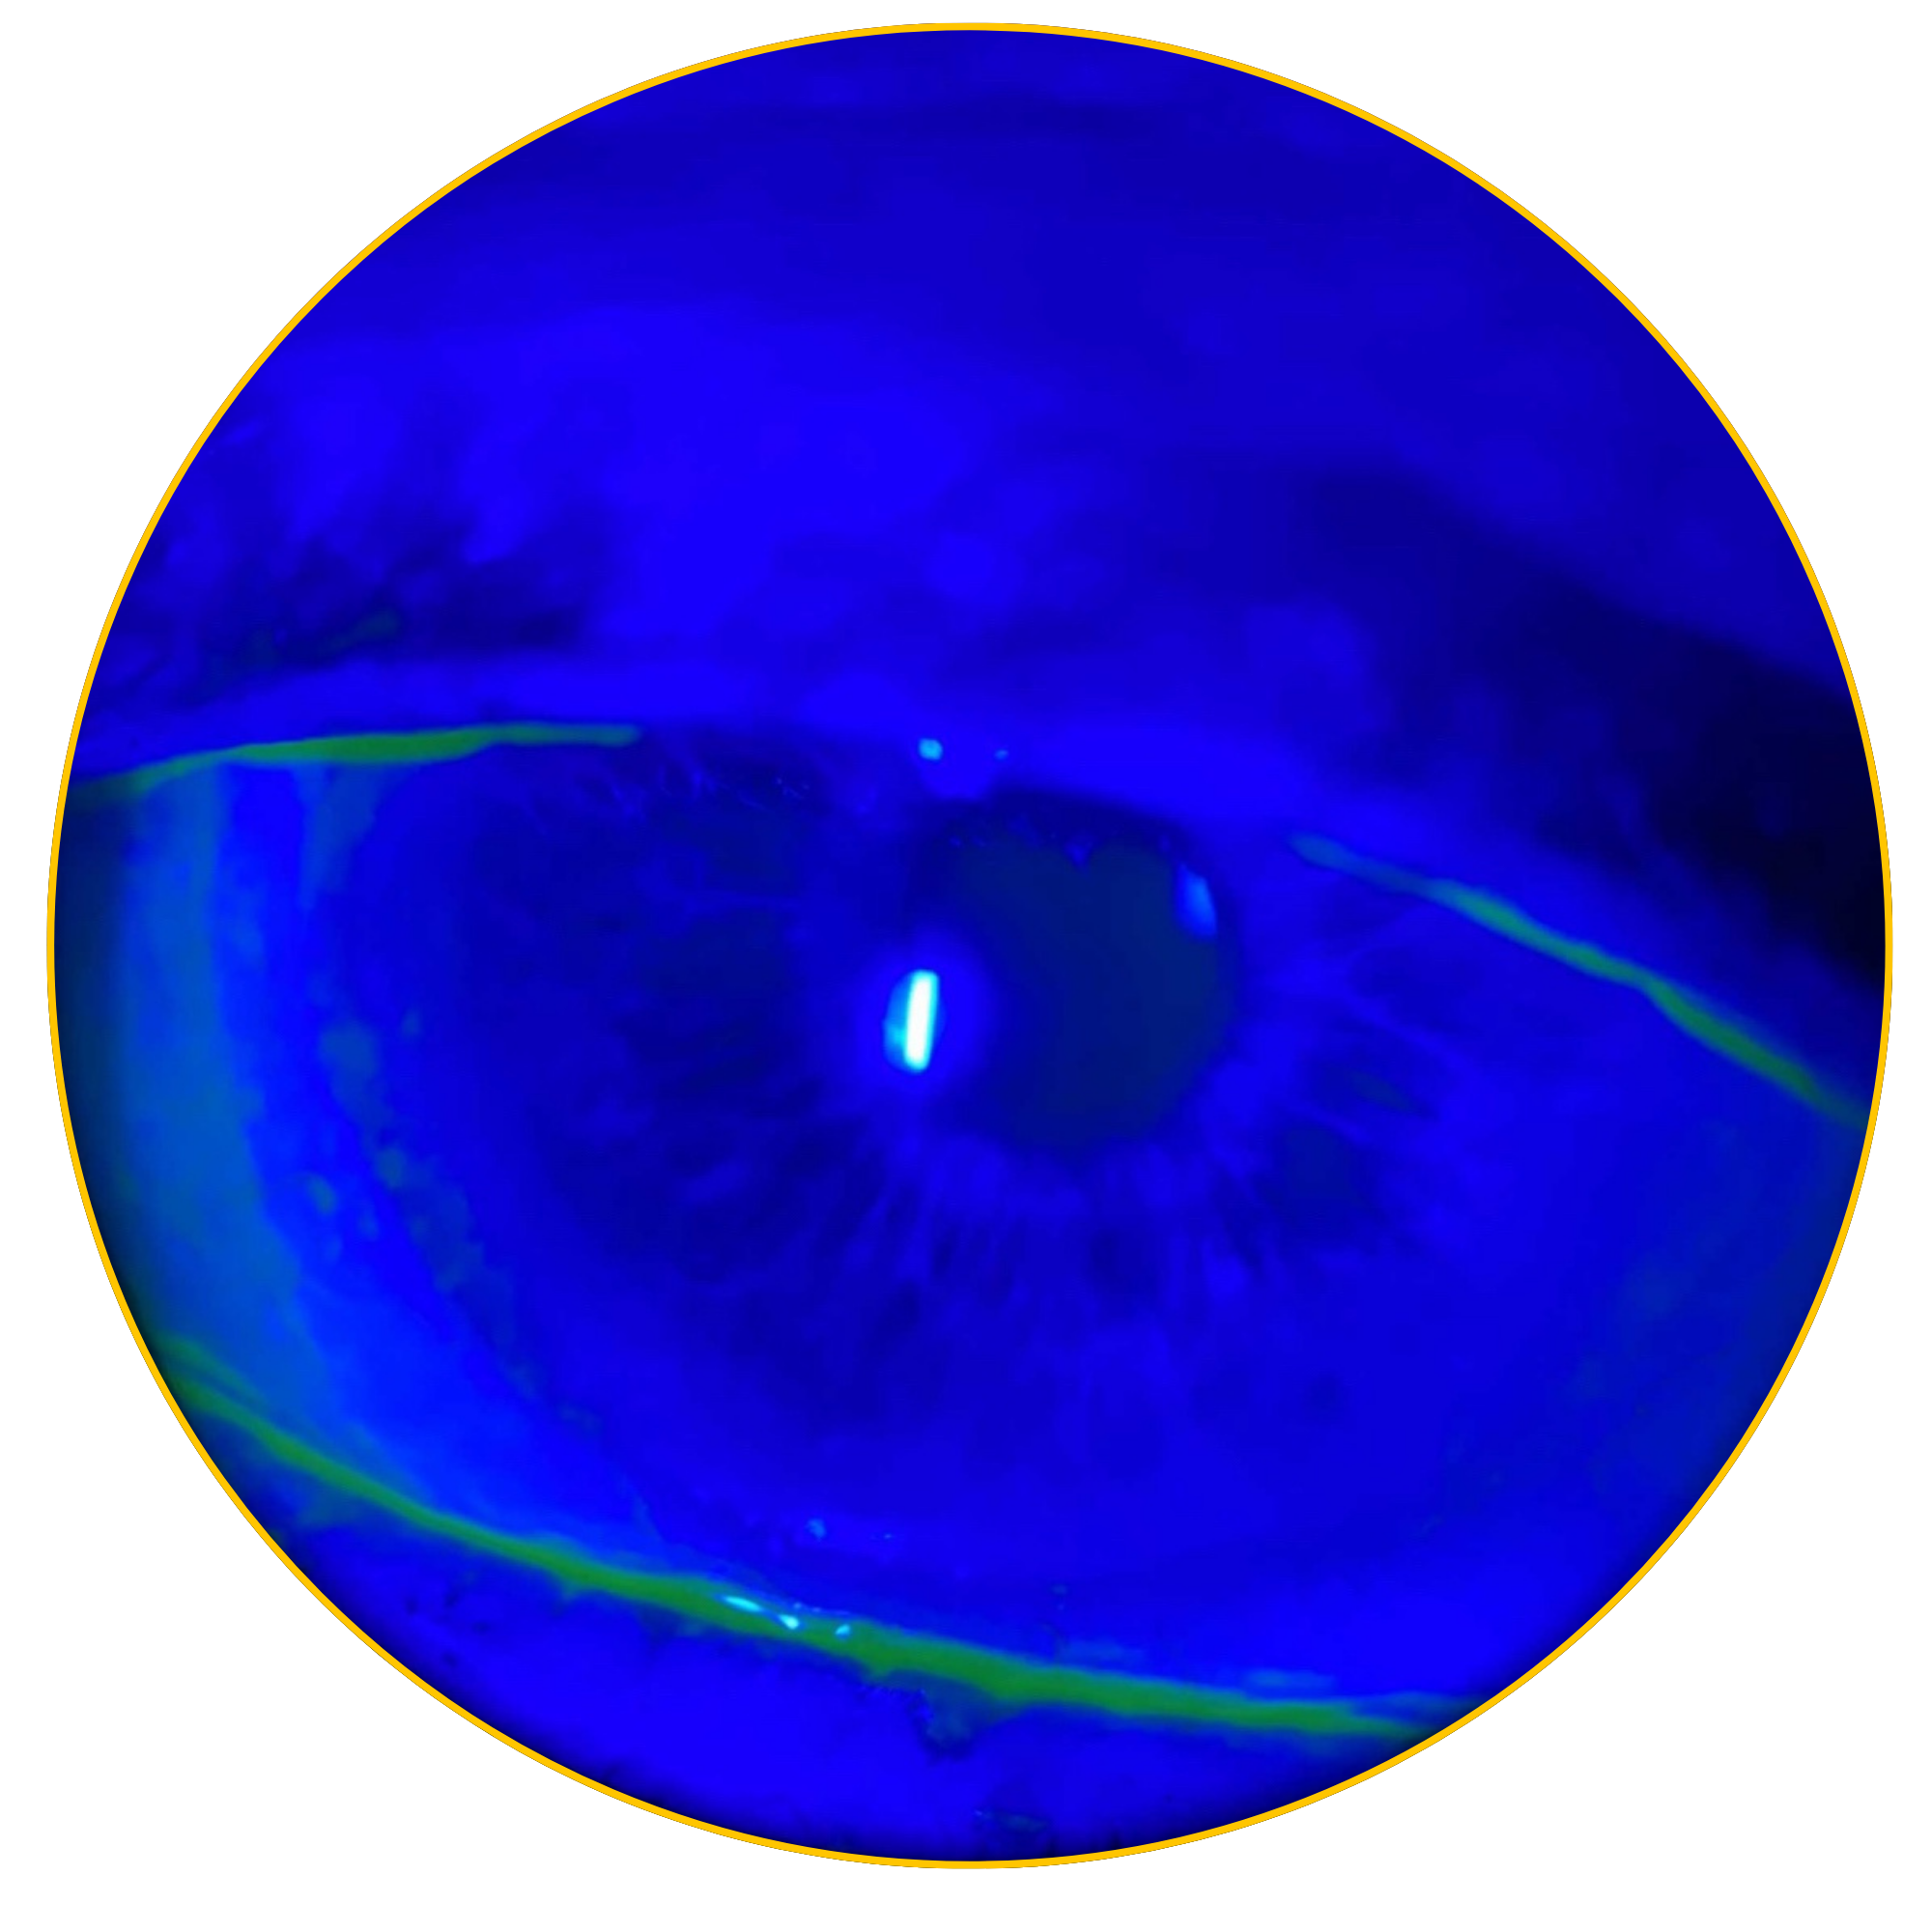

According to the Mackie classification, Stage 1 NK begins as early as Punctate Epithelial Keratitis (PEK).3 Lack of early detection can lead to corneal epithelial breakdown, impairment of healing, and development of corneal ulceration, melting, and perforation.4

Early detection & treatment are key to preventing further epithelial damage. Corneal sensitivity testing can help identify patients who may have underlying nerve damage and don’t respond to standard dry eye treatments.3 Detecting reduced sensitivity early can point to early stage Neurotrophic Keratitis and guide more targeted therapy to support healing and protect the cornea. Reduced corneal sensation affects nearly 10% of all eyes, and 30% of eyes with signs & symptoms of DED.1

As featured in Thomas John’s clinical study, there was a significant increase in corneal sensitivity from 1 to 3 months. This improvement was significantly correlated with the increase of corneal nerve density.7

CAM preserves innate complexes found in amniotic membrane tissue that help support the regeneration of corneal surface.8,9 In a clinical study, CAM is shown to reduce signs and symptoms in ocular surface disease and restore corneal nerve density, helping improve corneal sensitivity in patients with Dry Eye Disease. 7